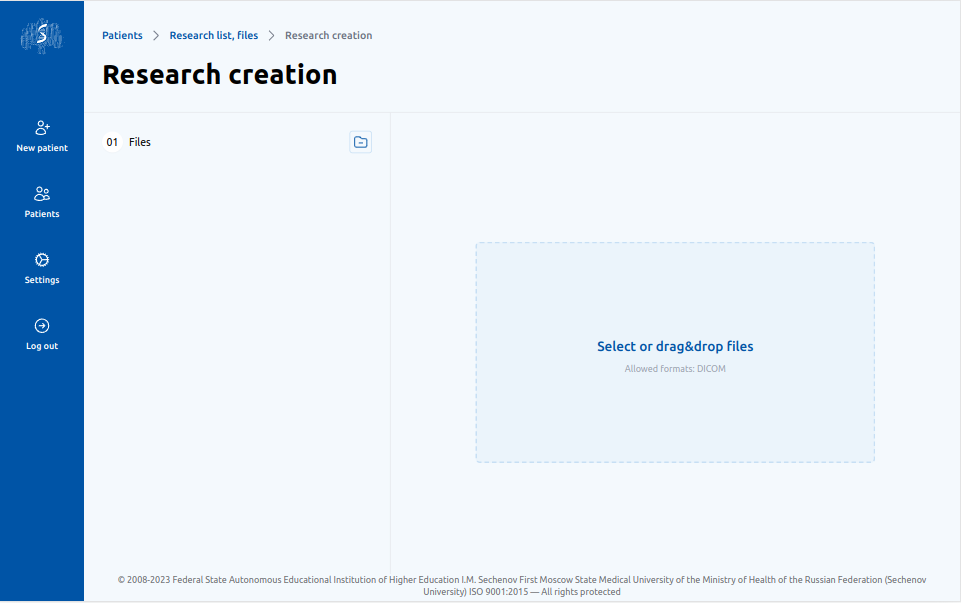

1

Загрузка снимков

Врач загружает снимки с 4мя контрастными фазами пациента